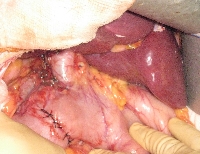

Πρόκειται για γυναίκα ασθενή 61 ετών, με αυξημένο BMI και ιστορικό σακχαρώδους διαβήτη, η οποία υποβλήθηκε σε ενδοσκοπικό υπέρηχο στα πλαίσια διερεύνησης ήπιας ανόδου της γGT και διάτασης του χοληδόχου πόρου. Αποκαλύφθηκε παραφατέρειο μόρφωμα μεγέθους ενός εκατοστού, η βιοψία του οποίου ανέδειξε in situ αδενοκαρκίνωμα. Η ασθενής υποβλήθηκε σε διαδωδεκαδακτυλική ληκυθεκτομή (Vater), με επανεμφύτευση του χοληδόχου και του παγκρεατικού πόρου (εικόνα 1), σε λεμφαδενικό καθαρισμό του χοληδόχου πόρου και του χώρου όπισθεν της παγκρεατικής κεφαλής (εικόνα 2), με εγκάρσια σύγκλιση του δωδεκαδακτύλου (εικόνα 3). Έλαβε εξιτήριο την 8η μετεγχειρητική ημέρα.